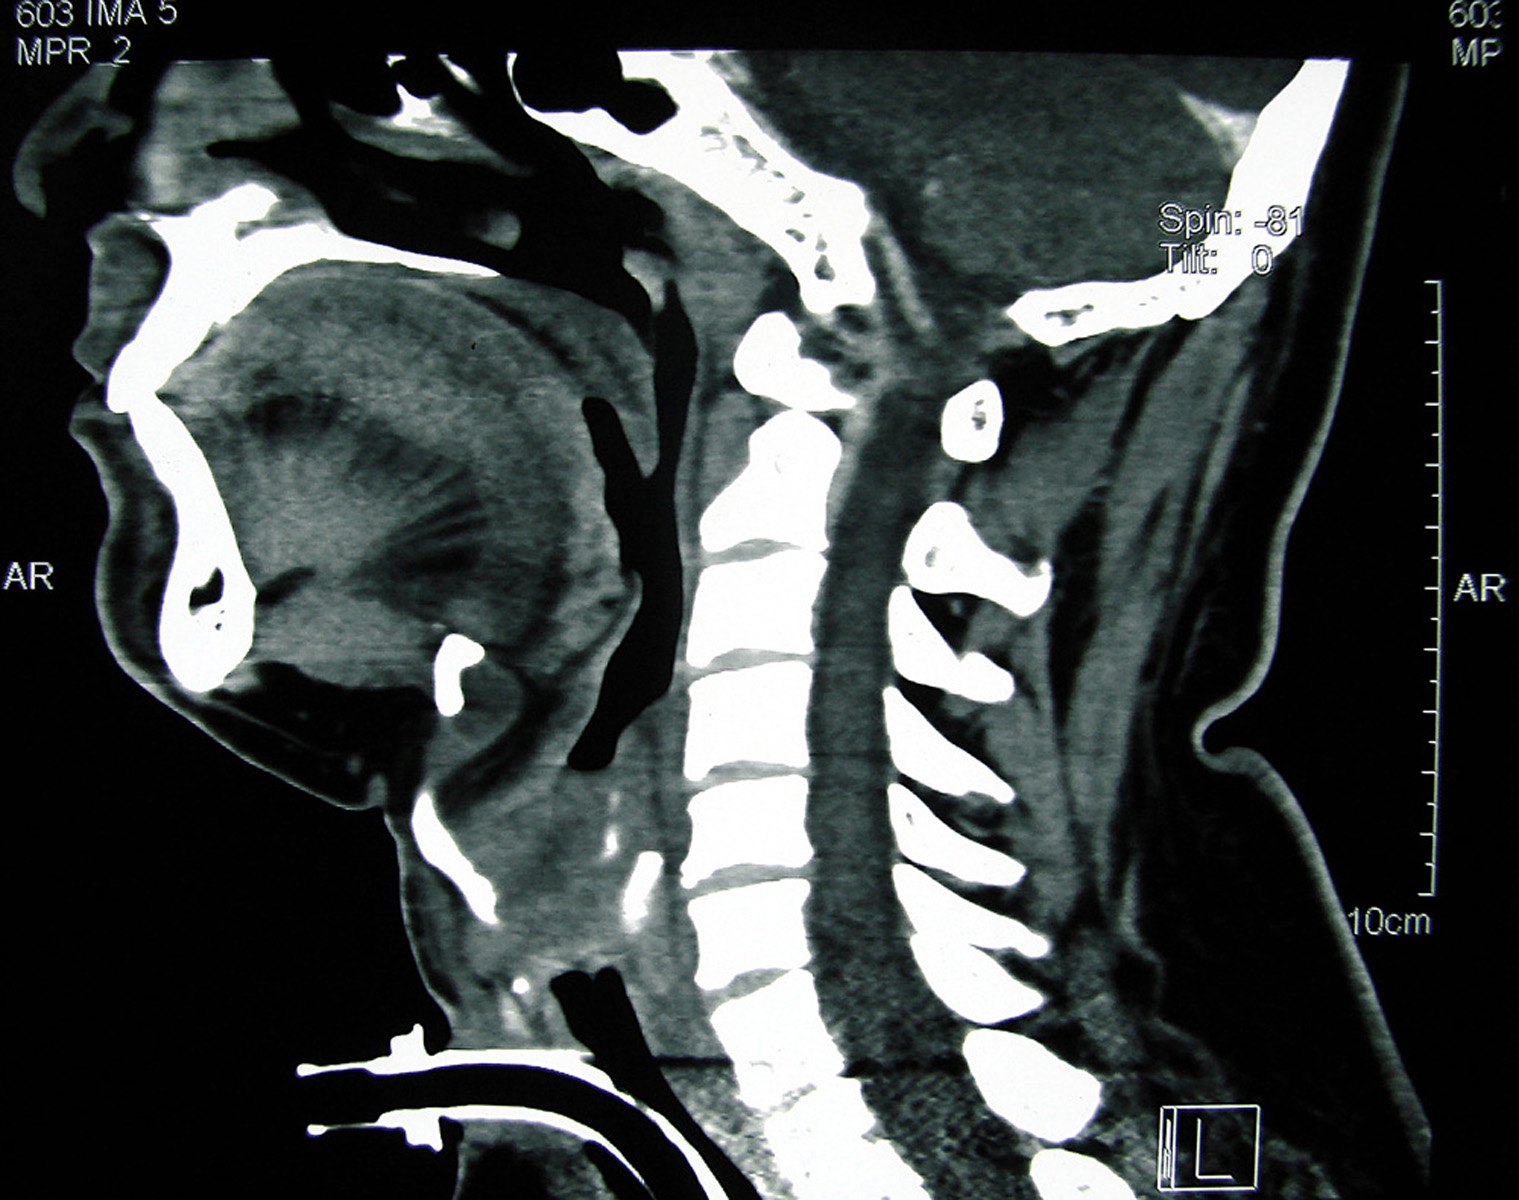

Spread of squamous cell carcinoma (SCC) commonly occurs vialocal lymphatic channels. Owing to scanty lymphatic drainage and vascular supply, SCC arising from the glottis rarely metastasizes. A 39-year-old male, operated for SCC of the glottis, presented 13 months later with complaints of headache. Computed tomography revealed a single ring-enhancing lesion in the right temporo-parietal region of the brain, suggestive of brain abscess. However, histopathological examination of the excised brain lesion showed metastasis of moderately differentiated SCC. Here, we report a rarecase of distant hematogenous brain metastasis of SCC of the glottis.